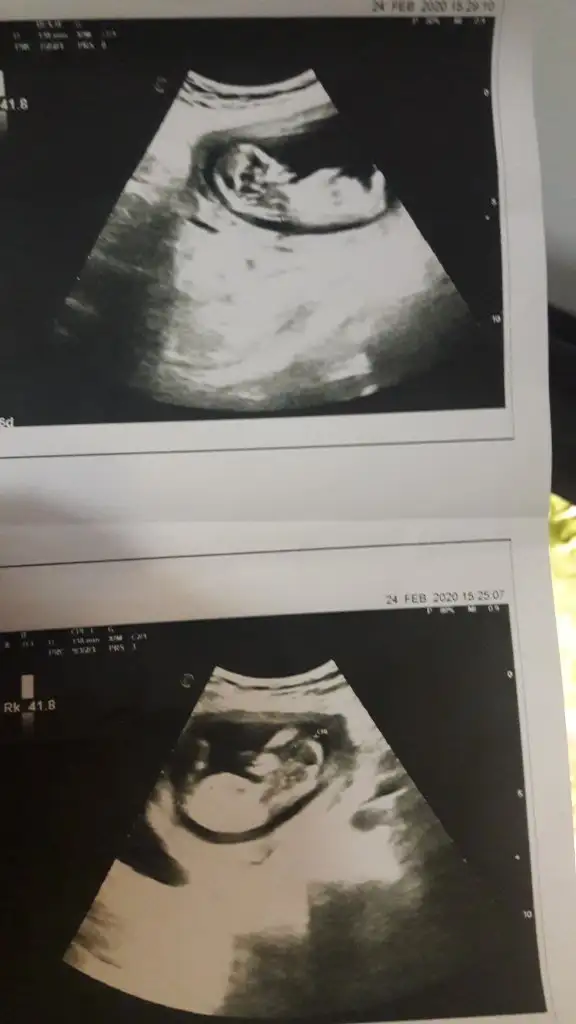

Ikra meyra Ikra meyra bize de bir yorum yapabilir misiniz? 11+5 haftalık görüntüsü

• IMG-20200223-WA0010.webp

IMG-20200223-WA0010.webp

17,9 KB · Görüntüleme: 83